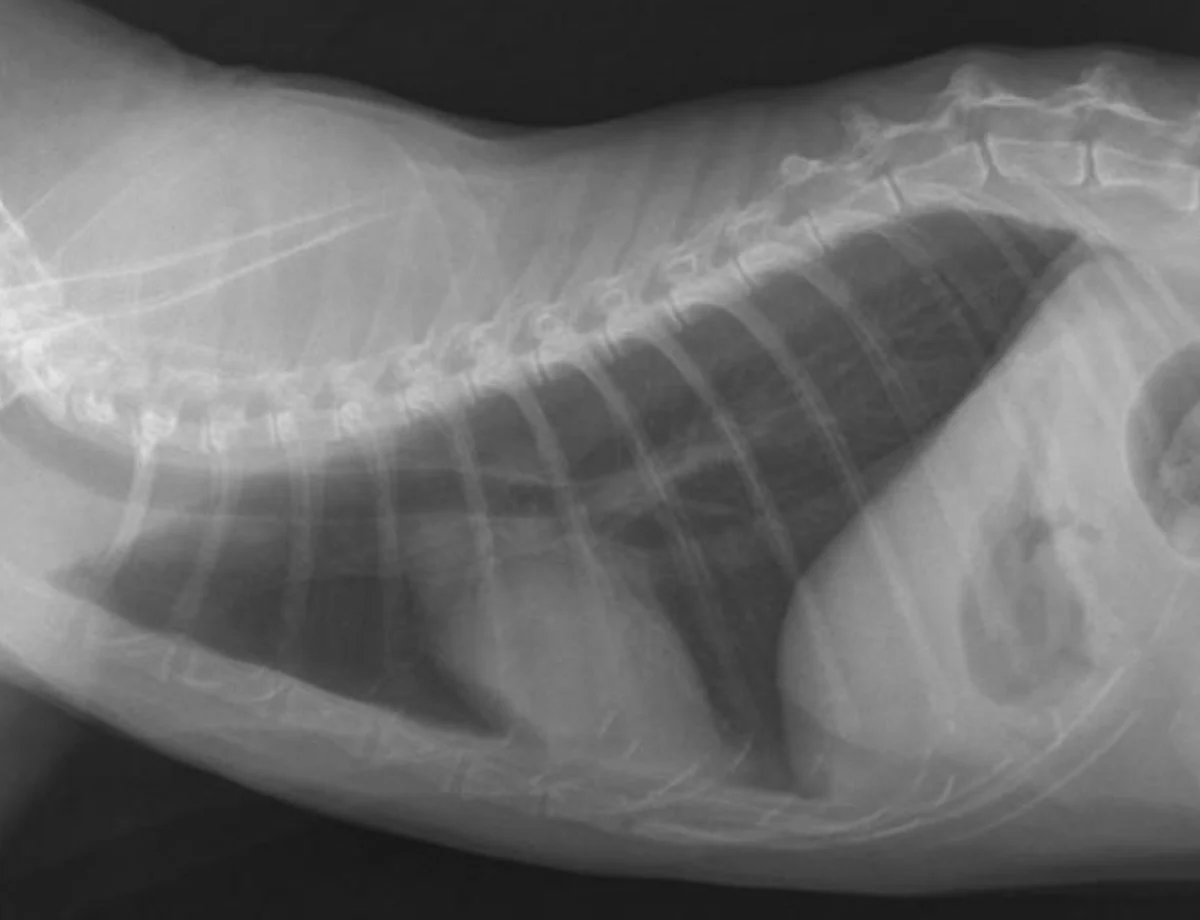

Remember to develop the films with fresh, clean developing solutions-old or exhausted developer will not work for developing technique charts. Examine the films for the setting that gives the best diagnostic quality. In Figure A, the kVp was 56, mA setting was 200, and time was 0.0125 seconds (mAs = 2.5). In this example, the bones are not easily visualized and the film overall is too white (underexposed).

In Figure B, the kVp and mA were left the same and the time was changed to 0.025 seconds (mAs = 5). In this image, the body wall, abdominal organs, and bones can all be readily visualized; this is a proper exposure. In Figure C, the kVp and mA were left the same and the time was changed to 0.05 seconds (mAs = 10). With this higher exposure technique, the ventral body wall cannot be visualized, and the abdomen is too dark (overexposed).

A